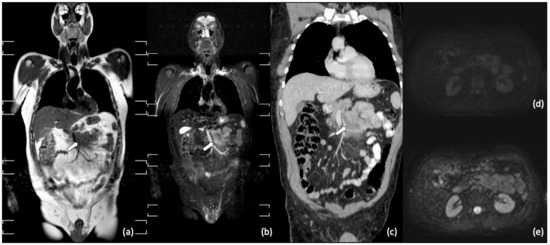

- Punwani, S.; Cheung, K.K.; Skipper, N.; Bell, N.; Bainbridge, A.; Taylor, S.A.; Groves, A.M.; Hain, S.F.; Ben-Haim, S.; Shankar, A.; et al. Dynamic contrast-enhanced MRI improves accuracy for detecting focal splenic involvement in children and adolescents with Hodgkin disease. Pediatr. Radiol. 2013, 43, 941–949. [Google Scholar] [CrossRef]

- Littooij, A.S.; Kwee, T.C.; Barber, I.; Granata, C.; De Keizer, B.; Beek, F.J.; Hobbelink, M.G.; Fijnheer, R.; Stoker, J.; Nievelstein, R.A. Accuracy of whole-body MRI in the assessment of splenic involvement in lymphoma. Acta Radiol. 2015, 57, 142–151. [Google Scholar] [CrossRef] [PubMed]